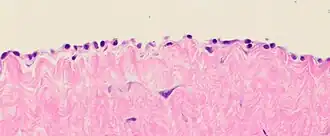

Cytology of the normal mesothelial cells that line the peritoneum, with typical features.[9] Wright's stain -